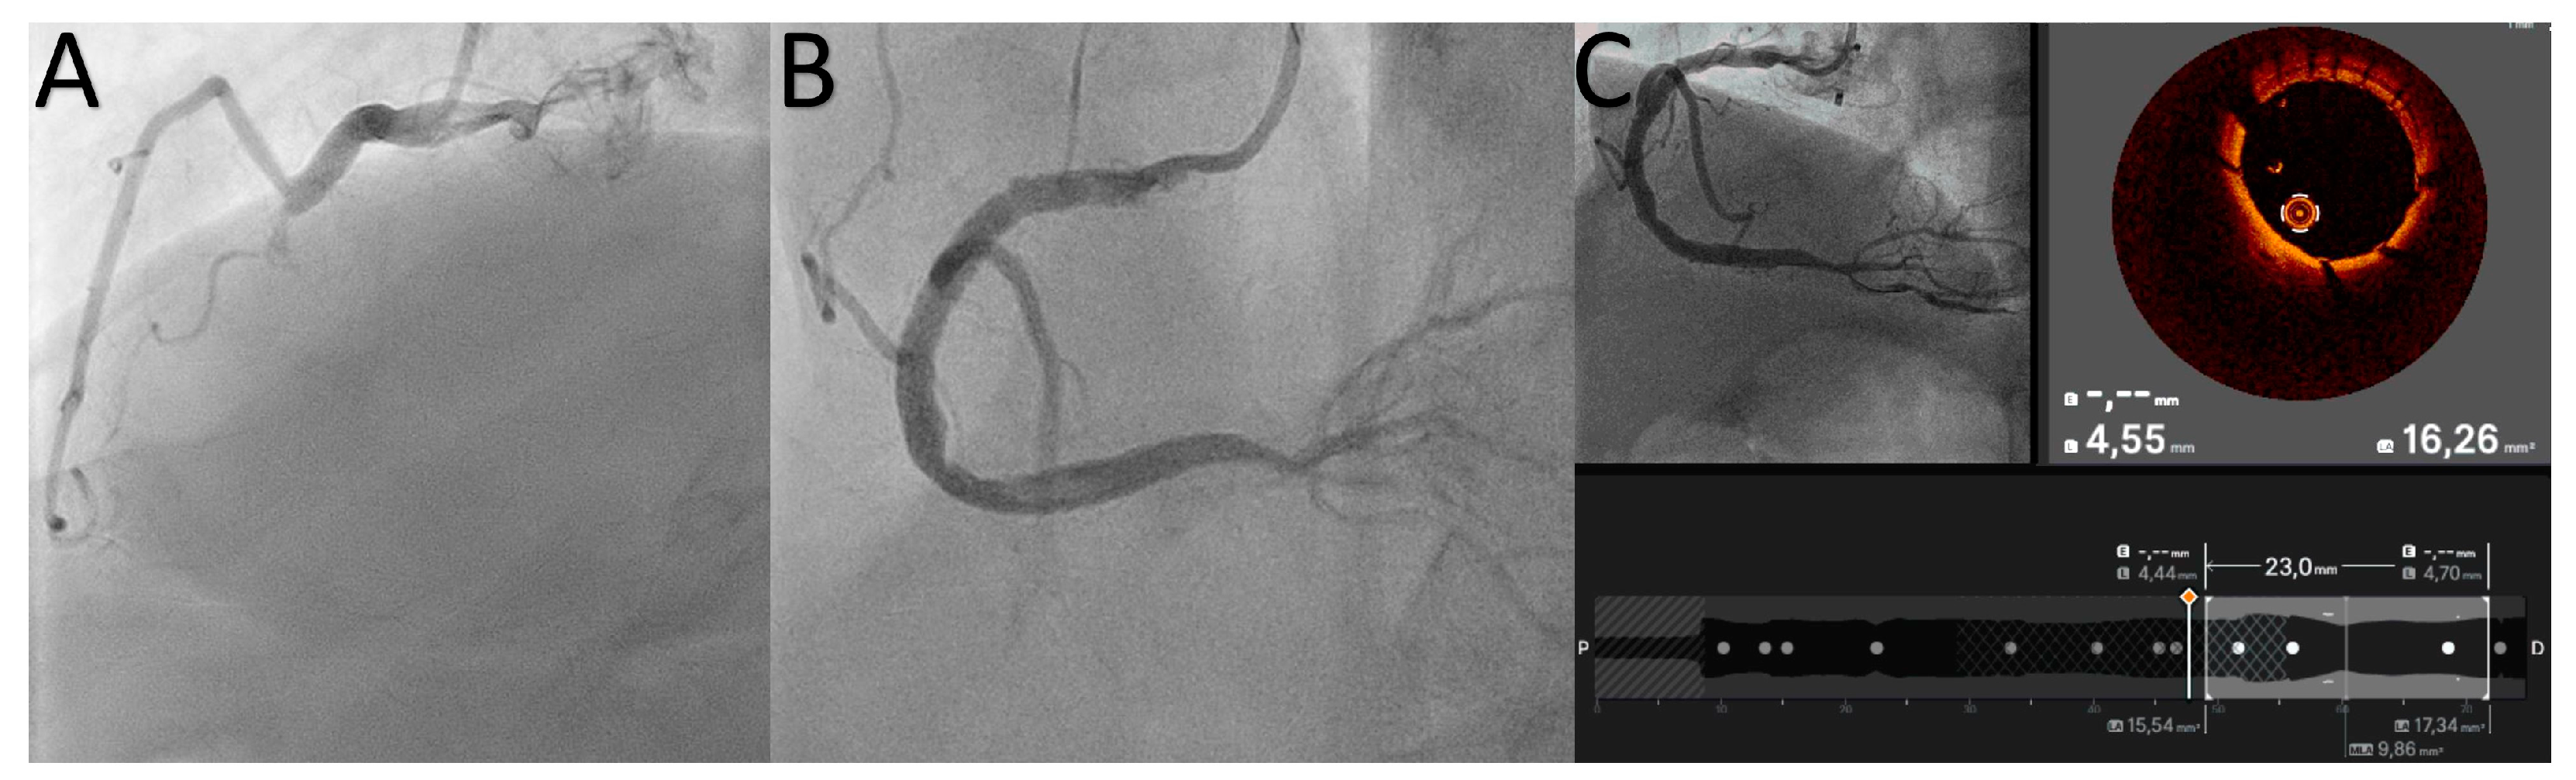

2.1. Proximal Cap Ambiguity

2.4. Stent Deployment and Optimization